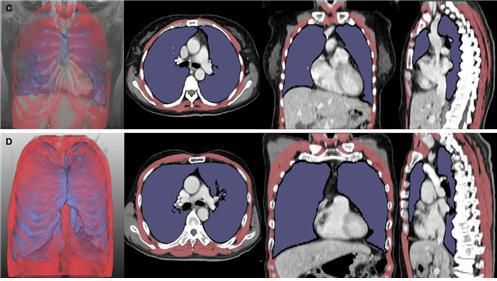

5개월(위)과 43개월(아래) 생존한 루게릭병 환자의 흉부 컴퓨터단층촬영(CT) 영상 분석 내용. 위의 환자는 폐 용적 지수(LVI·보라색)와 호흡근 용적 지수(RMI·빨간색)가 아래 환자보다 낮게 나타났다. 서울대병원 제공 |

이러한 문제 해결을 위해 연구진은 인공지능(AI)을 이용, 루게릭병 환자의 폐와 호흡근육 위축 정도를 나타내는 폐 용적 지수(LVI)와 호흡근 용적 지수(RMI)를 개발했다. 그런 다음 루게릭병 환자 261명의 흉부 CT 영상을 분석, 루게릭병 병기‧생존기간과의 연관성을 확인했다. RMI는 폐와 호흡근의 부피를 키의 제곱으로 나눈 값이다.

연구진에 따르면, 폐·호흡근 용적 지수는 루게릭병 병기(1~4기)가 높아질수록 유의미하게 감소했고, 해당 지수를 통한 환자의 예후 평가 정확도는 기존 폐활량 검사와 큰 차이가 없었다. 폐·호흡근 용적 지수가 낮은 환자군은 높은 환자군보다 호흡근육 위축이 뚜렷했으며, 기관절개술을 받거나 사망에 이르는 시점도 빨랐다. 기관절개술은 호흡근육이 약해진 루게릭병 환자에게 시행하는 것으로, 목 부위를 절개해 인공 기도관을 삽입하는 수술이다.